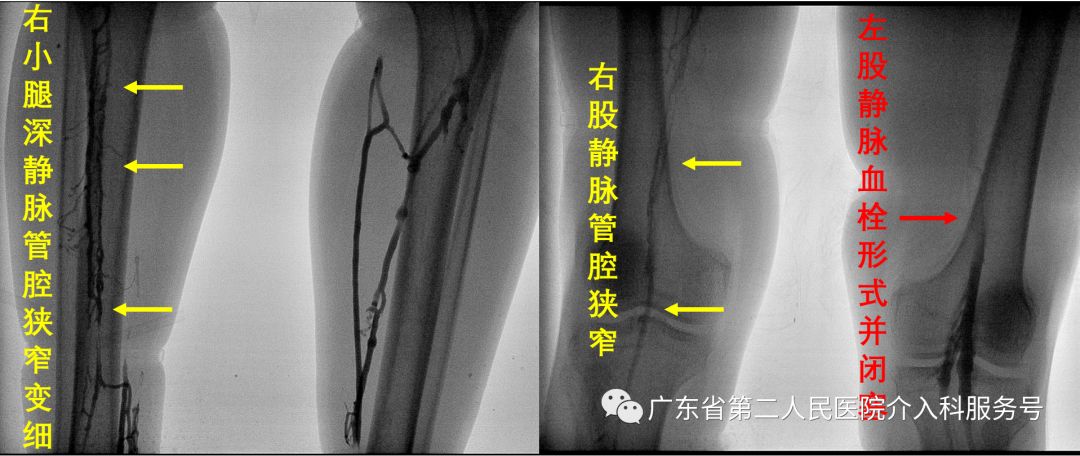

冯先生由当地医院转至我院,我院经双足造影显示:右下肢深静脉管腔明显变窄,呈慢性血栓再通表现;左小腿深静脉显影尚可,显影静脉内无血栓形成,大腿股静脉内大量血栓形成并闭塞,左髂总静脉、髂外静脉及下腔静脉不显影(如下图)。

经右股静脉与左腘静脉插管造影如下图